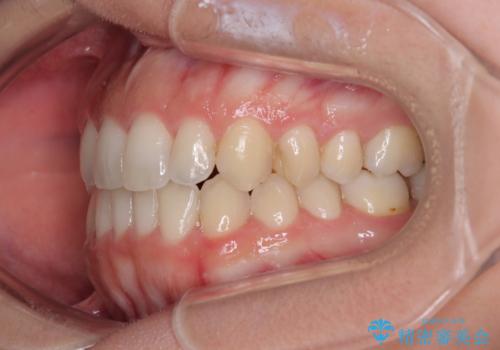

【モニター】オープンバイトをインビザライン矯正で治す

- 前歯の開咬を気にして来院された患者様です。

開咬の治療は、前歯を閉じるように動かすとともに、上下臼歯を圧下(骨内にめり込ませる)させることで進めて行きます。

インビザラインは臼歯の圧下を効果的に行えるため、インビザラインを用いて矯正治療を行うこととしました。